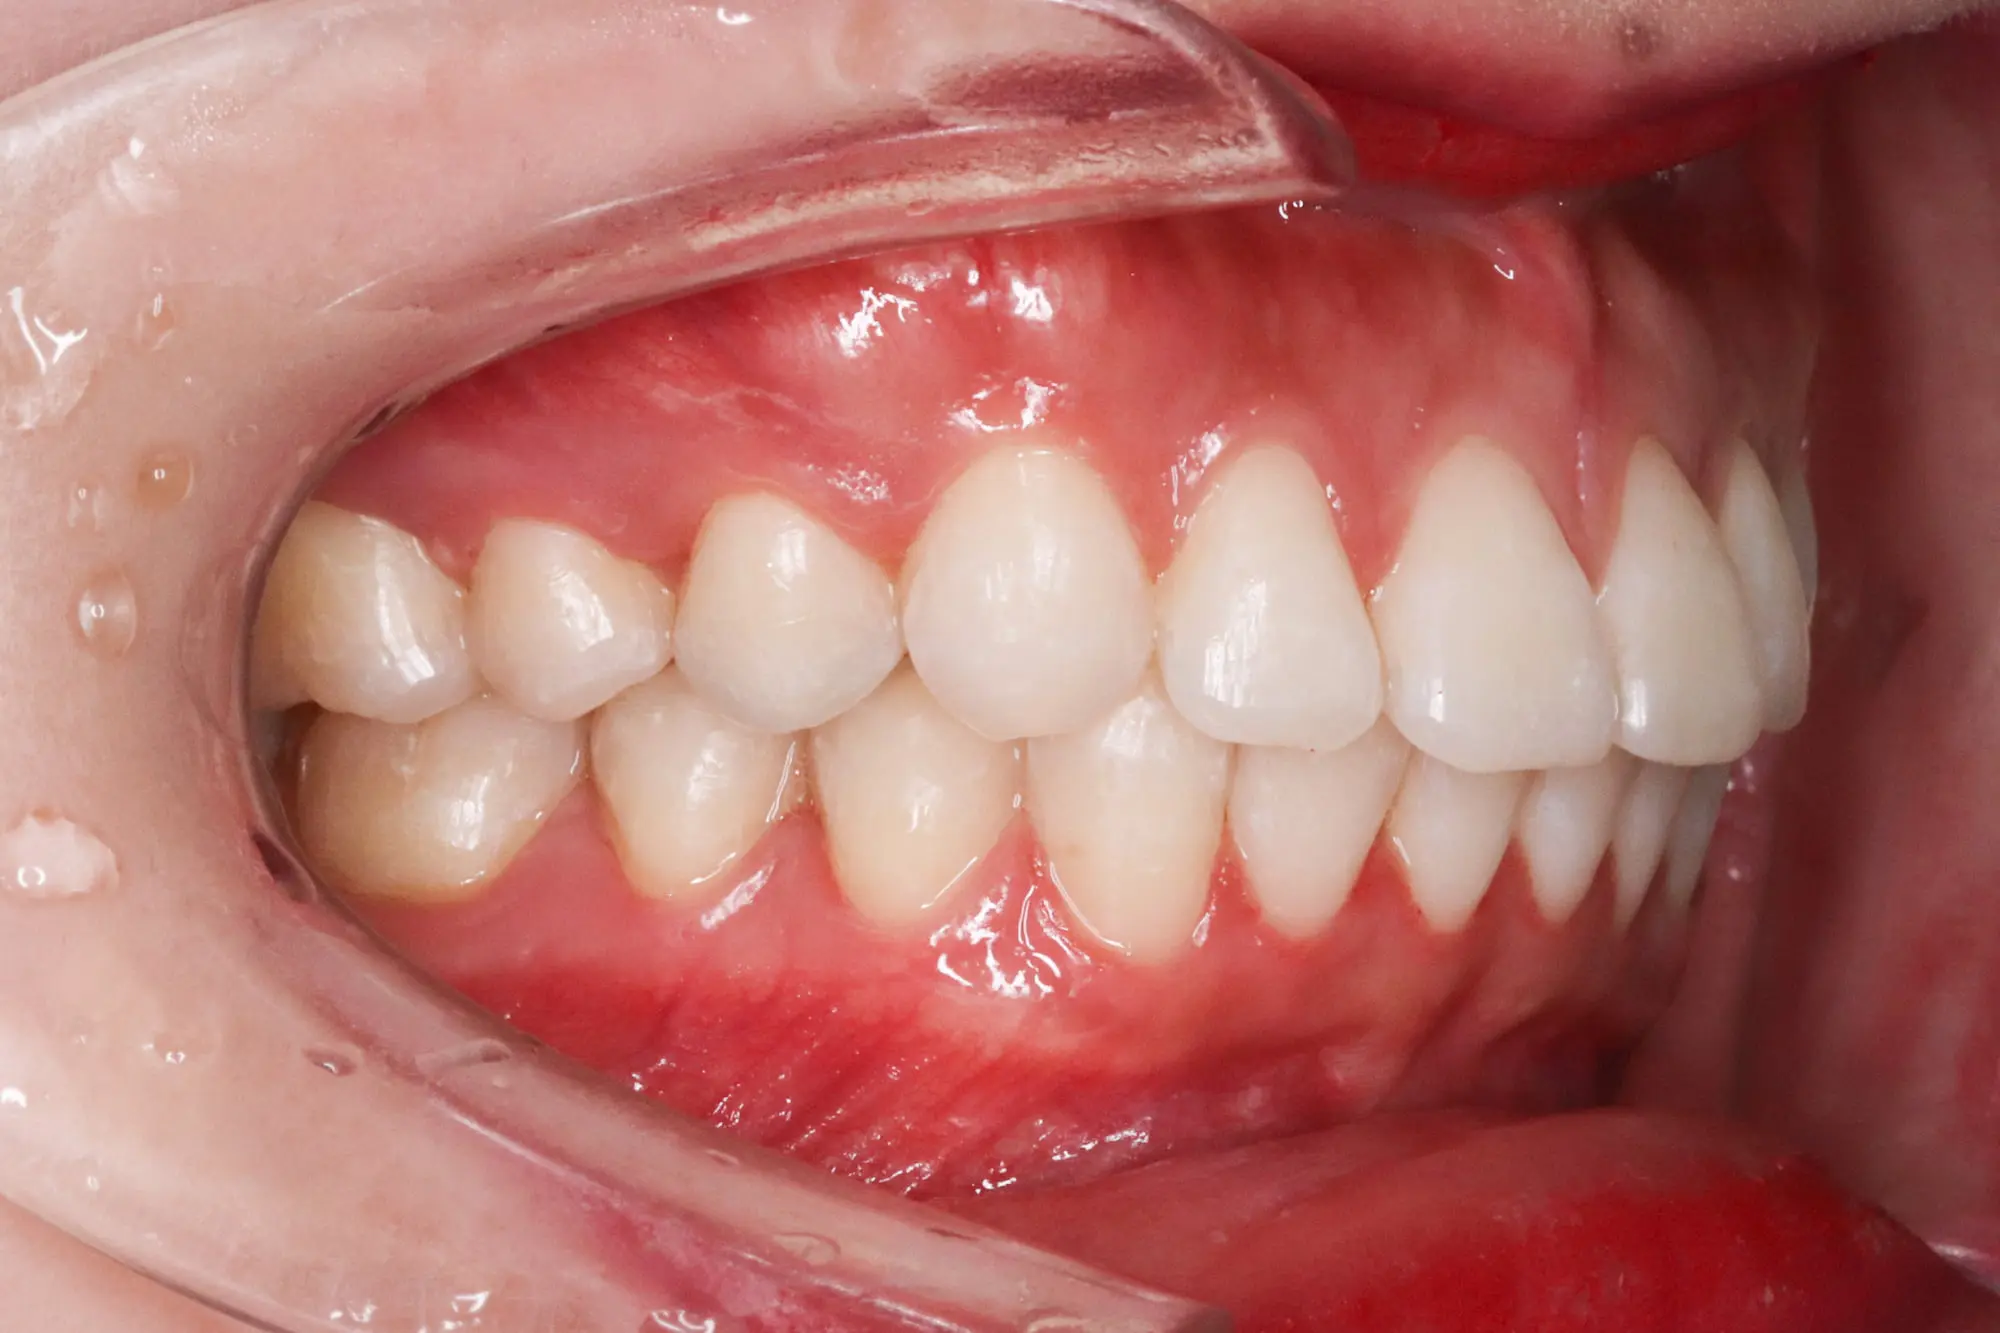

After

Crowding